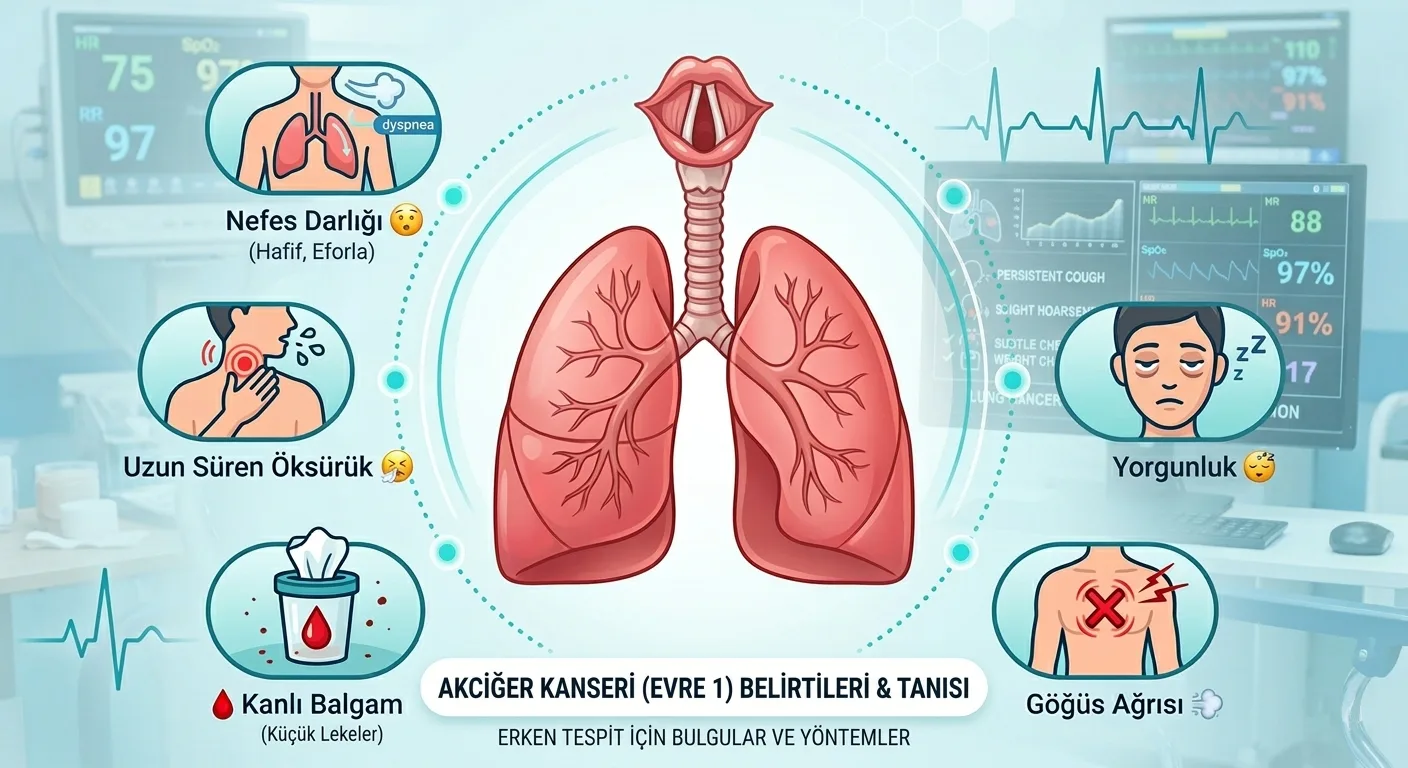

EVRE 1

EVRE 1

Tümör sadece akciğerdedir ve lenf bezlerine sıçramamıştır.